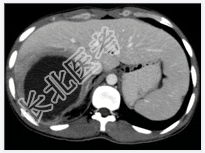

- [材料题] 患者男性,25岁,因发热.肝区疼痛2周入院。2周前患者无明显诱因出现高热.肝区疼痛,血常规检查白细胞及中性粒细胞明显升高。体查.肝肋缘下1cm可触及,且有明显触痛。行上腹部CT增强扫描+三维重建。

- 简答题1、患者的诊断及依据是什么?

- 简答题2、鉴别诊断有哪些?